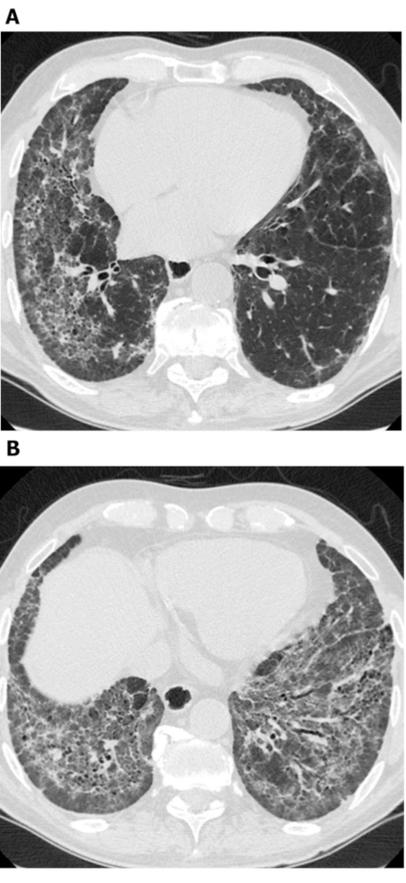

谢谢你的邀请,先普及一下肺GGO及肺GGN定义,通俗的讲肺GGO就是肺内的磨玻璃密度影,肺GGN为肺内磨玻璃结节,大众通常所说的应该是磨玻璃结节。

第三当我们发现GGN后,我们医生应该怎样客观对待它,而不至于误诊,患者怎样对待它而不至于恐慌。这又谈到肺结节话题了,我们这次只聊GGN,它又分纯磨玻璃结节PGGN和混合性磨玻璃结节mGGN, 混合性的往往恶性的可能性又大点,碰到这种结节,我们一般有经验的放射科医生或临床医生,结合患者临床病史及影像学变现,都能判断个八九不离十,对于可疑恶性结节,也行只有很牛的专家才能判断,往往很牛专家号都很难挂,这时常规就是处理原则就是短期随访,同时可以结合临床辅助抗炎治疗,短期随访复查,观察结节的变化再定其性质。最后我们放射科及临床都不怀疑的结节,那就常规半年或一年随访,对于这种结节,你完全没有必要恐慌,就算恐慌,你也无能为力,基本上所有医生都说不像是恶性的,随访吧,那我们就安心的随访吧,不然我们还能做些什么呢?

目前,如果发现有肺GGO,尤其是结节的直径在1cm以下时,建议进行HRCT扫描。目前的HRCT扫描厚度为1-2mm,基本上只要是有经验的专科医生认真阅片,不太会遗漏。

很多病人发现GGO后非常紧张,常拿着打印的CT胶片甚至仅拿着一纸报告就到处求诊,要求明确结节的性质,这对医生来说真的很困难。因为,打印的胶片和电子版的图像在清晰度上是无法相比的,而且电子图像多数还可以调整图像大小并进行CT值测定等一系列操作,便于医生更好的鉴别。因此,如果发现肺内GGO,建议携电子影像就诊。

至于“误诊”,实际上几乎没有哪位专业的医生敢于仅仅是阅片后就告诉你这个GGO “100%”是什么。最肯定的情况下,多数医生也会说“极有可能是......”,或者“很像......”。尤其是纯粹的GGO,就是不含任何实性成分的肺磨玻璃结节,原因很多,单靠影像学是不能确诊的,所以谈不上“误诊”。如果GGO比较大,直径达到8mm以上,有早期肺癌的可能,病人本人就非常焦虑,可以考虑手术切除。只有手术后的病理检查结果才能告知明确的答案。